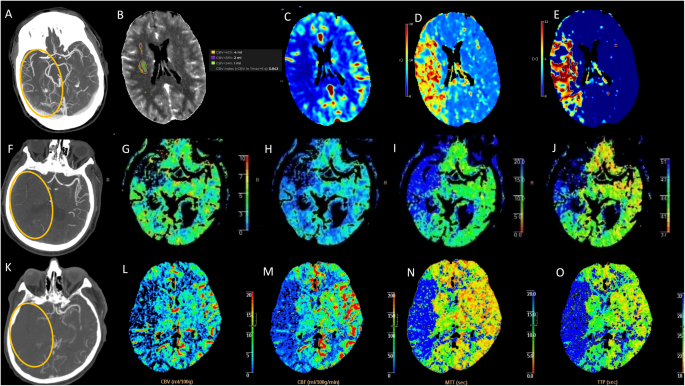

We enrolled 101 patients with LVO AIS, 37 males (36.6%) and 64 females (63.4%); mean ±SD age 76.4 ±12.4 years. Twenty-nine patients (28.5%) had a wake-up stroke or unknown onset of symptoms. Patients were divided into three groups according to the collateral status: poor, intermediate and good collaterals (Figure 1).

The figure illustrates three representative cases of leptomeningeal collateral status—good, intermediate, and poor—in patients with acute LVO stroke. The first row shows a case of LVO involving the M1 segment of the right middle cerebral artery (MCA) with good collateral circulation, as indicated by CTA (circle in A). The corresponding perfusion maps demonstrate a large ischemic penumbra supported by robust collateral flow (CBV in B; CBF in C; MTT in D; and Tmax in E). The second row presents a case with intermediate collateral circulation (circle in F). The associated perfusion maps reveal a smaller penumbra (CBV in G; CBF in H; MTT in I; and TTP in J), indicating moderate collateral support. The third row depicts a case with poor collateral circulation (circle in K). The corresponding perfusion maps show no significant ischemic penumbra, suggesting insufficient collateral perfusion. LVO: large vessel occlusion; MCA: middle cerebral artery; CBV: cerebral blood volume; CBF: cerebral blood flow; MTT: mean transit time; Tmax: time to maximum; TTP: time to peak.